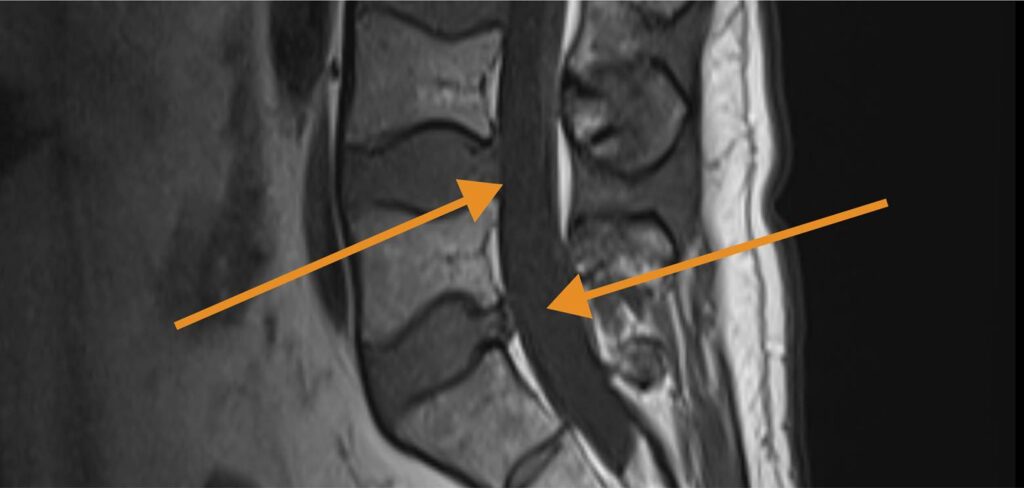

- Spinal injuries including several herniated and torn discs

Lewis’s doctors recommended surgery to address pain, compressed nerves, and ongoing mobility issues.

Lewis ultimately followed his doctors’ advice and underwent a minimally invasive procedure that involved:

- Removal of herniated disc fragments using a small camera and specialized tools

- Enlarging the nerve openings to relieve pressure on nerve roots

- Ablation (burning) of damaged nerve fibers to reduce joint pain